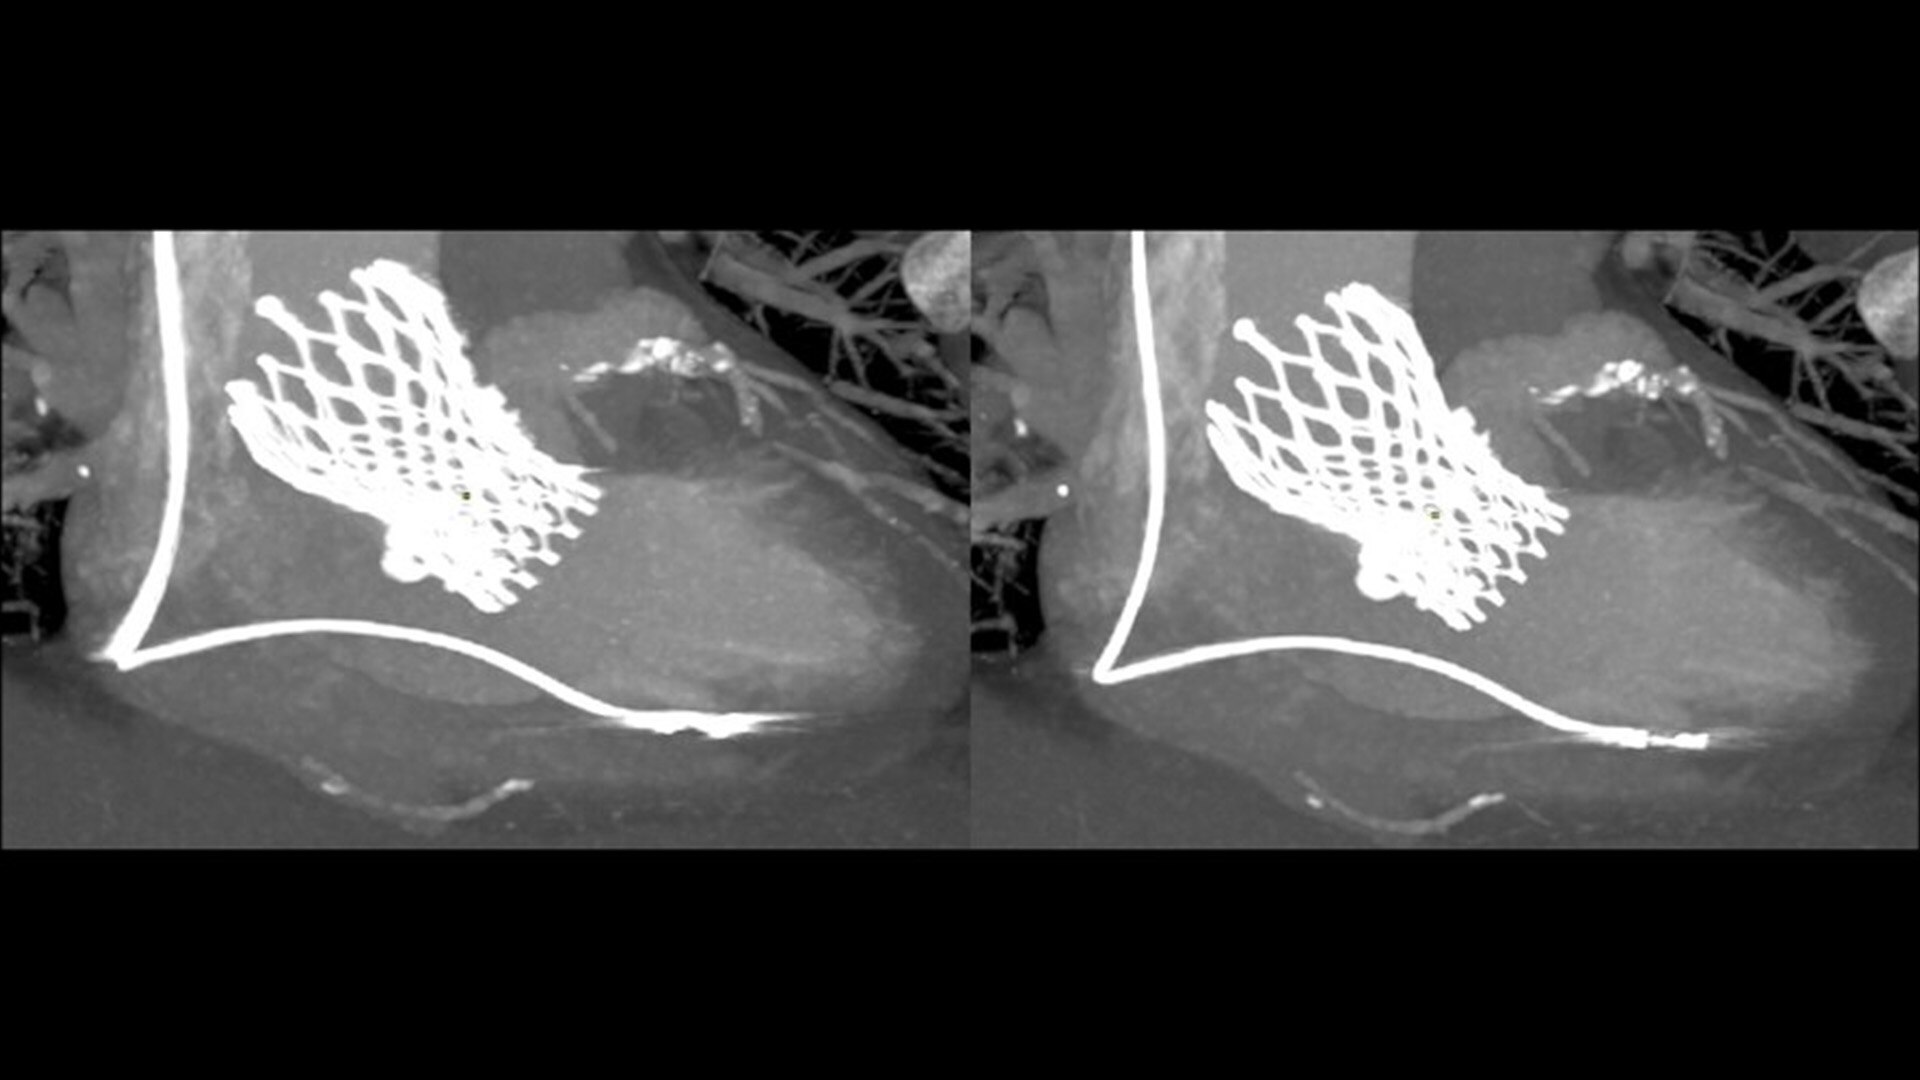

SnapShot Freeze 2

Intelligent and automated whole-heart motion correction for enhanced Cardiac CT imaging.

6x reduction in motion artifacts1

19.5 msec effective temporal resolution at 0.23s/rotation gantry speed2

Whole-heart motion correction

1. As demonstrated in mechanical and mathematical cardiac phantom testing

2. SnapShot Freeze 2, in conjunction with 0.23 s/rotation gantry speed, provides a reduction in coronary motion artifacts that is equivalent to a 0.039 s/rotation equivalent gantry rotation speed with effective temporal resolution of 19.5 msec. As demonstrated in phantom testing using a commercially available motion phantom and also with a mathematical cardiac phantom with linear motion of variable velocity. The 0.039 s/rotation images are modeled without application of SnapShot Freeze 2. Results may vary in clinical applications.